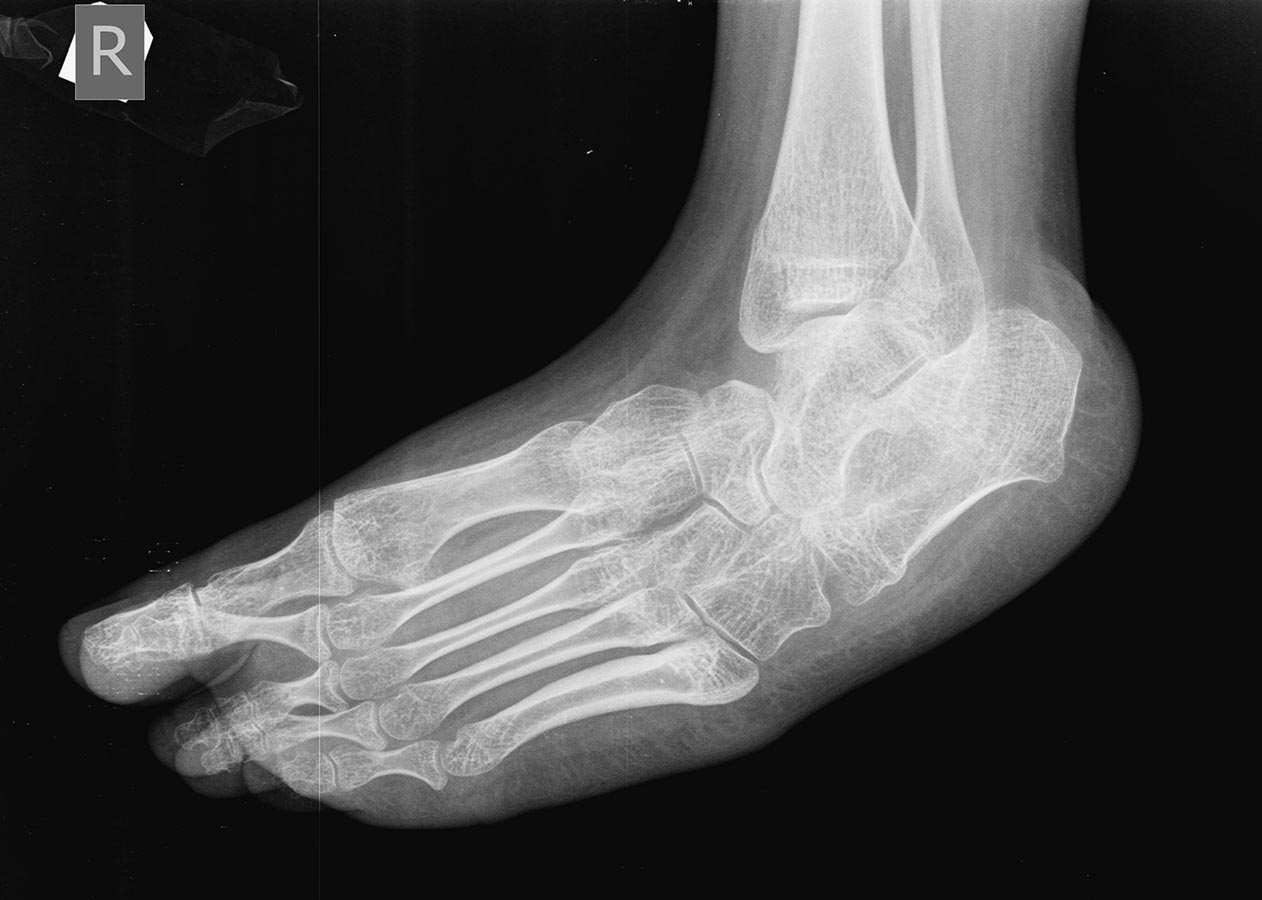

Девочка 15-и лет, страдает ДЦП, квадриплегия, хорошо "разработана", в

8-и летнем возрасте была проведена тенотомия икроножных мышц в

подколенной ямке и приводящих, периодически проходит агрессивную

разработку. До последнего времни могла ходит при помощи палочки, на

ногах AFO. Последний год из-за выраженной эквино-варусной деформации

обеих стоп не может носить ортезы и всвязи с этим ходит при помощи

поддержки матери, стала "колясочной". Учится на отлично! Пассивно стопы

выводятся из эквинуса спокойно, до +5 градусов тыльного

сгибания, в подтаранных суставах пассивные движения отсутствуют,